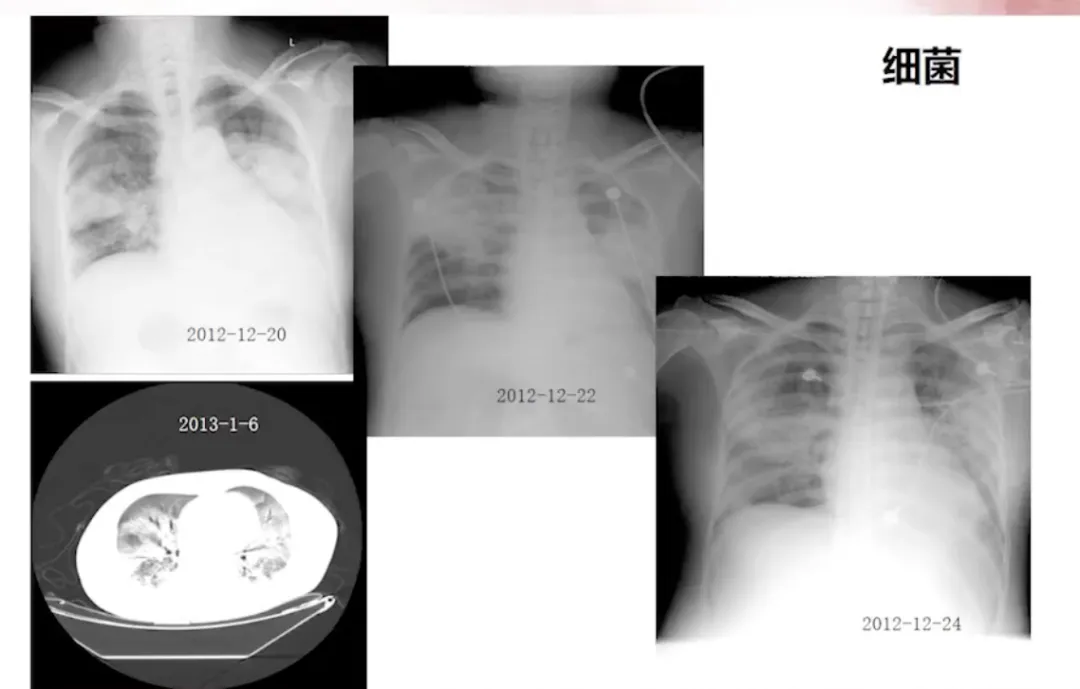

脓毒症的处理